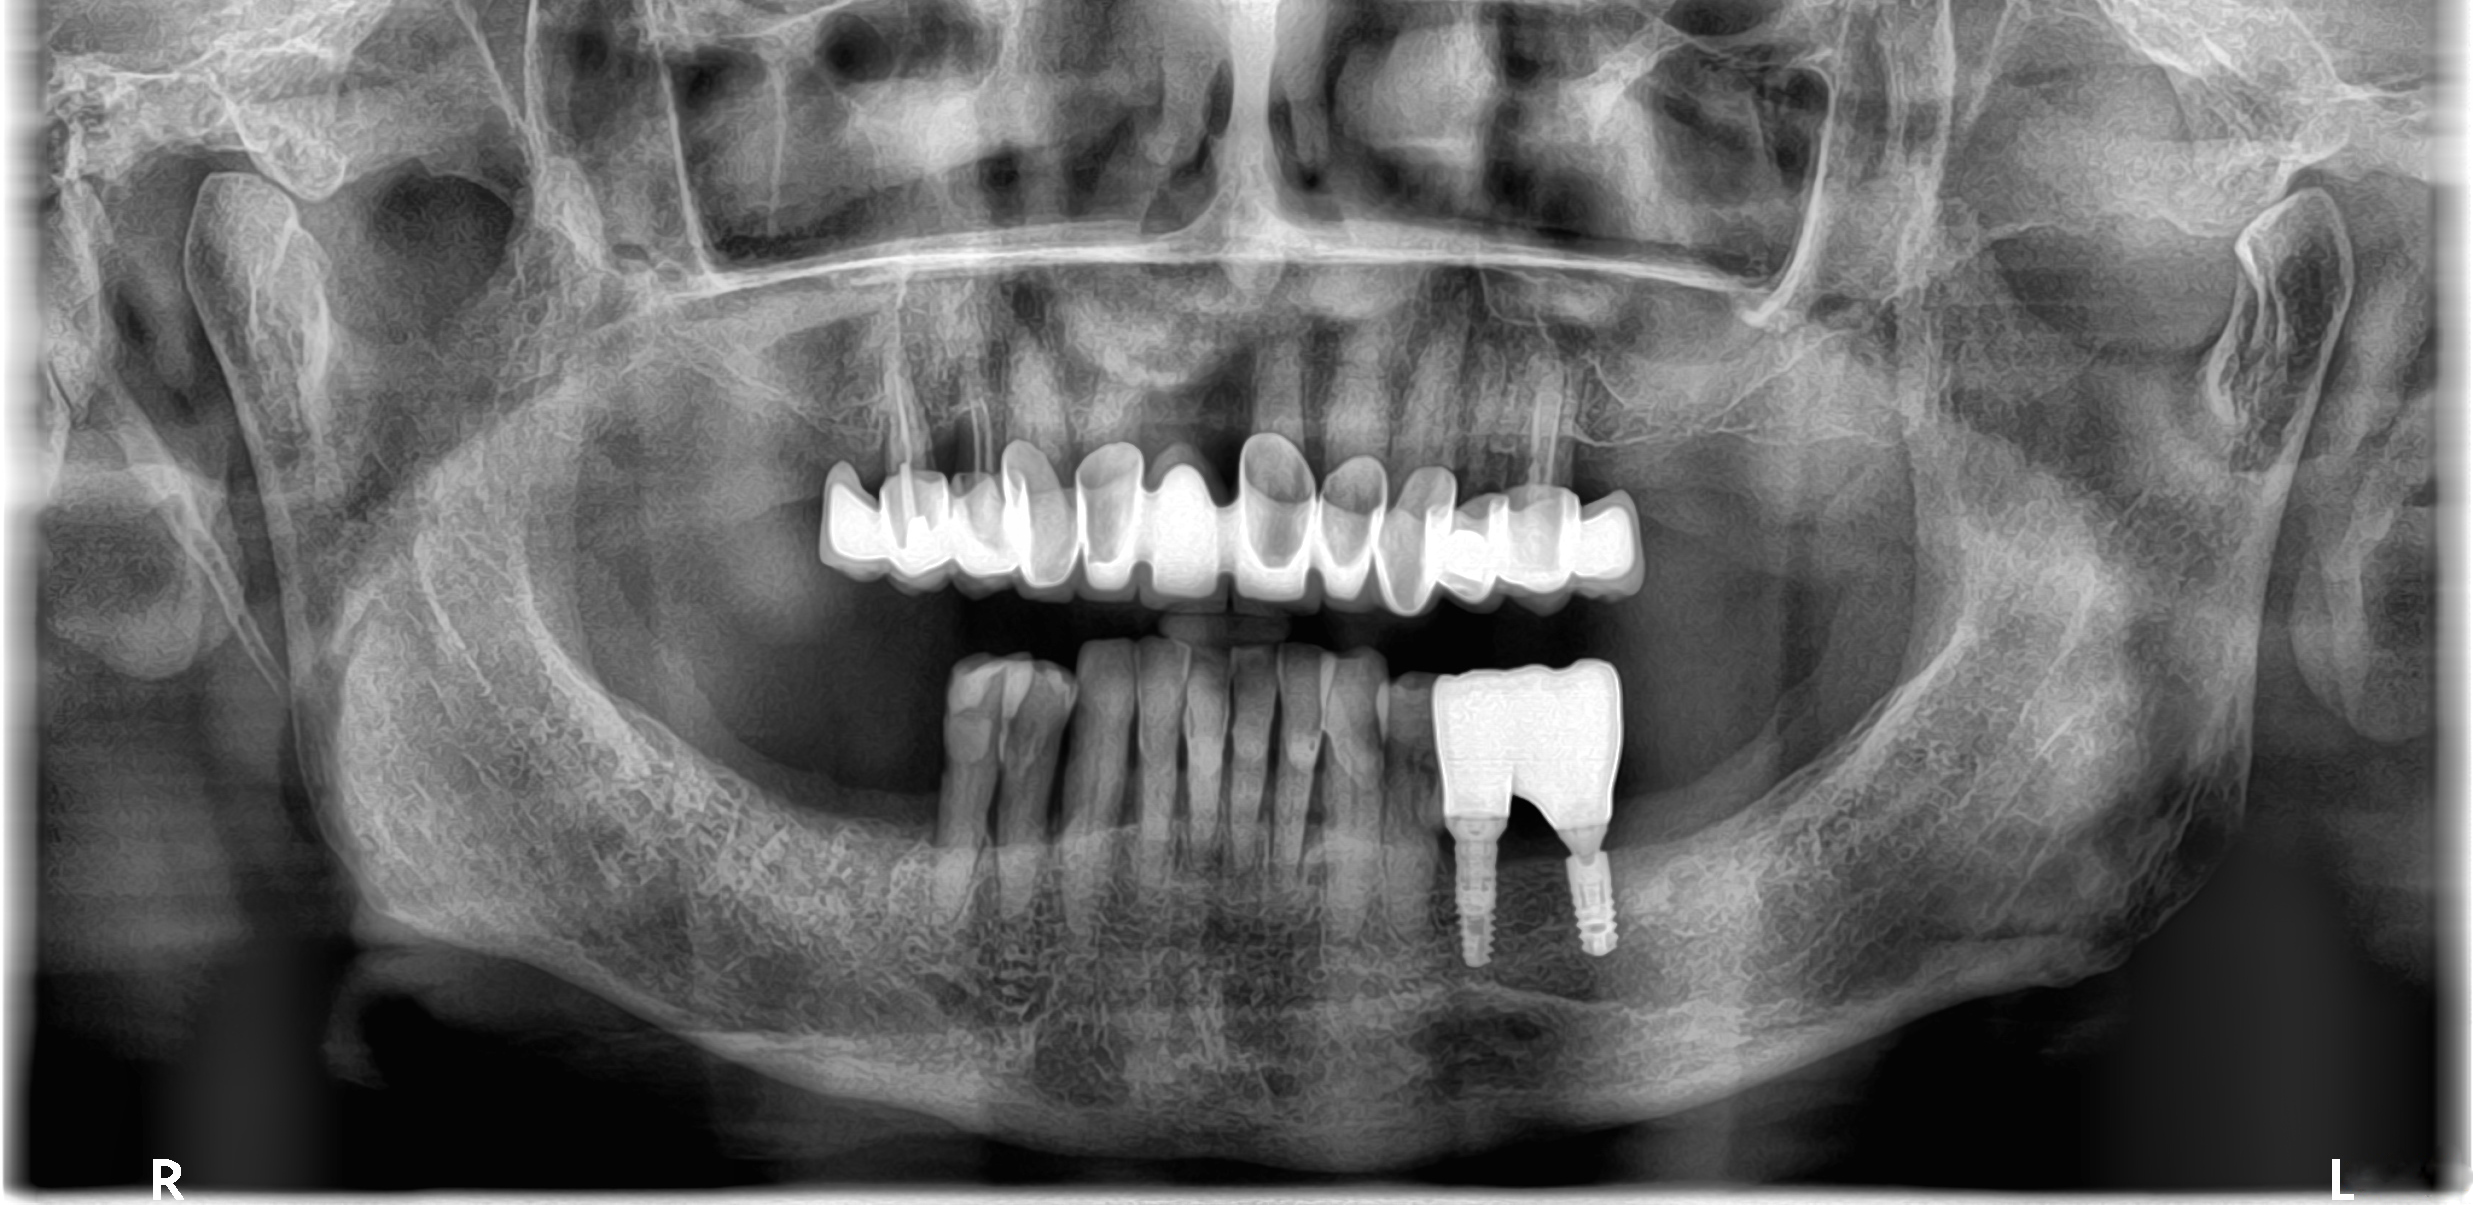

Αρχική κατάσταση - Πανοραμική ακτινογραφία -  Έλλειψη των κάτω δεξιά γομφίων

Ασθενής προσήλθε στο Aesthetic Dental Studio στην Καλαμάτα με απώλεια δύο οπισθίων δοντιών (1ος και 2ος γομφίος) στη δεξιά πλευρά της κάτω γνάθου. Ζητούσε μια μόνιμη, σταθερή λύση αποκατάστασης χωρίς τη χρήση κινητής οδοντοστοιχίας. Η θεραπευτική μας προσέγγιση βασίστηκε στην ψηφιακή τεχνολογία και τον εξατομικευμένο σχεδιασμό για το καλύτερο αισθητικό και λειτουργικό αποτέλεσμα.

Παράλληλα, αποφασίστηκε η λήψη τρισδιάστατης αξονικής ακτινογραφίας (CBCT) για αξιολόγηση του διαθέσιμου οστού και του ανατομικού χώρου, ως απαραίτητο βήμα πριν την τοποθέτηση των εμφυτευμάτων.